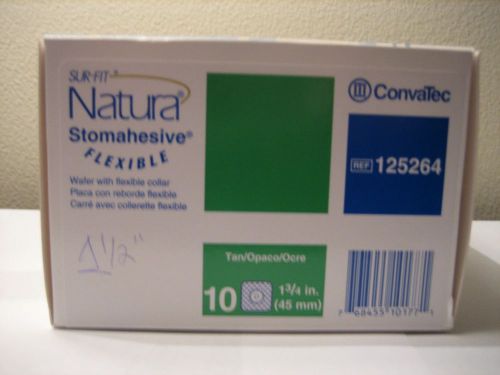

Convatec Sur-fit Natura Stomahesive Pre-Cut Flexible Wafer 125264 1 /34"